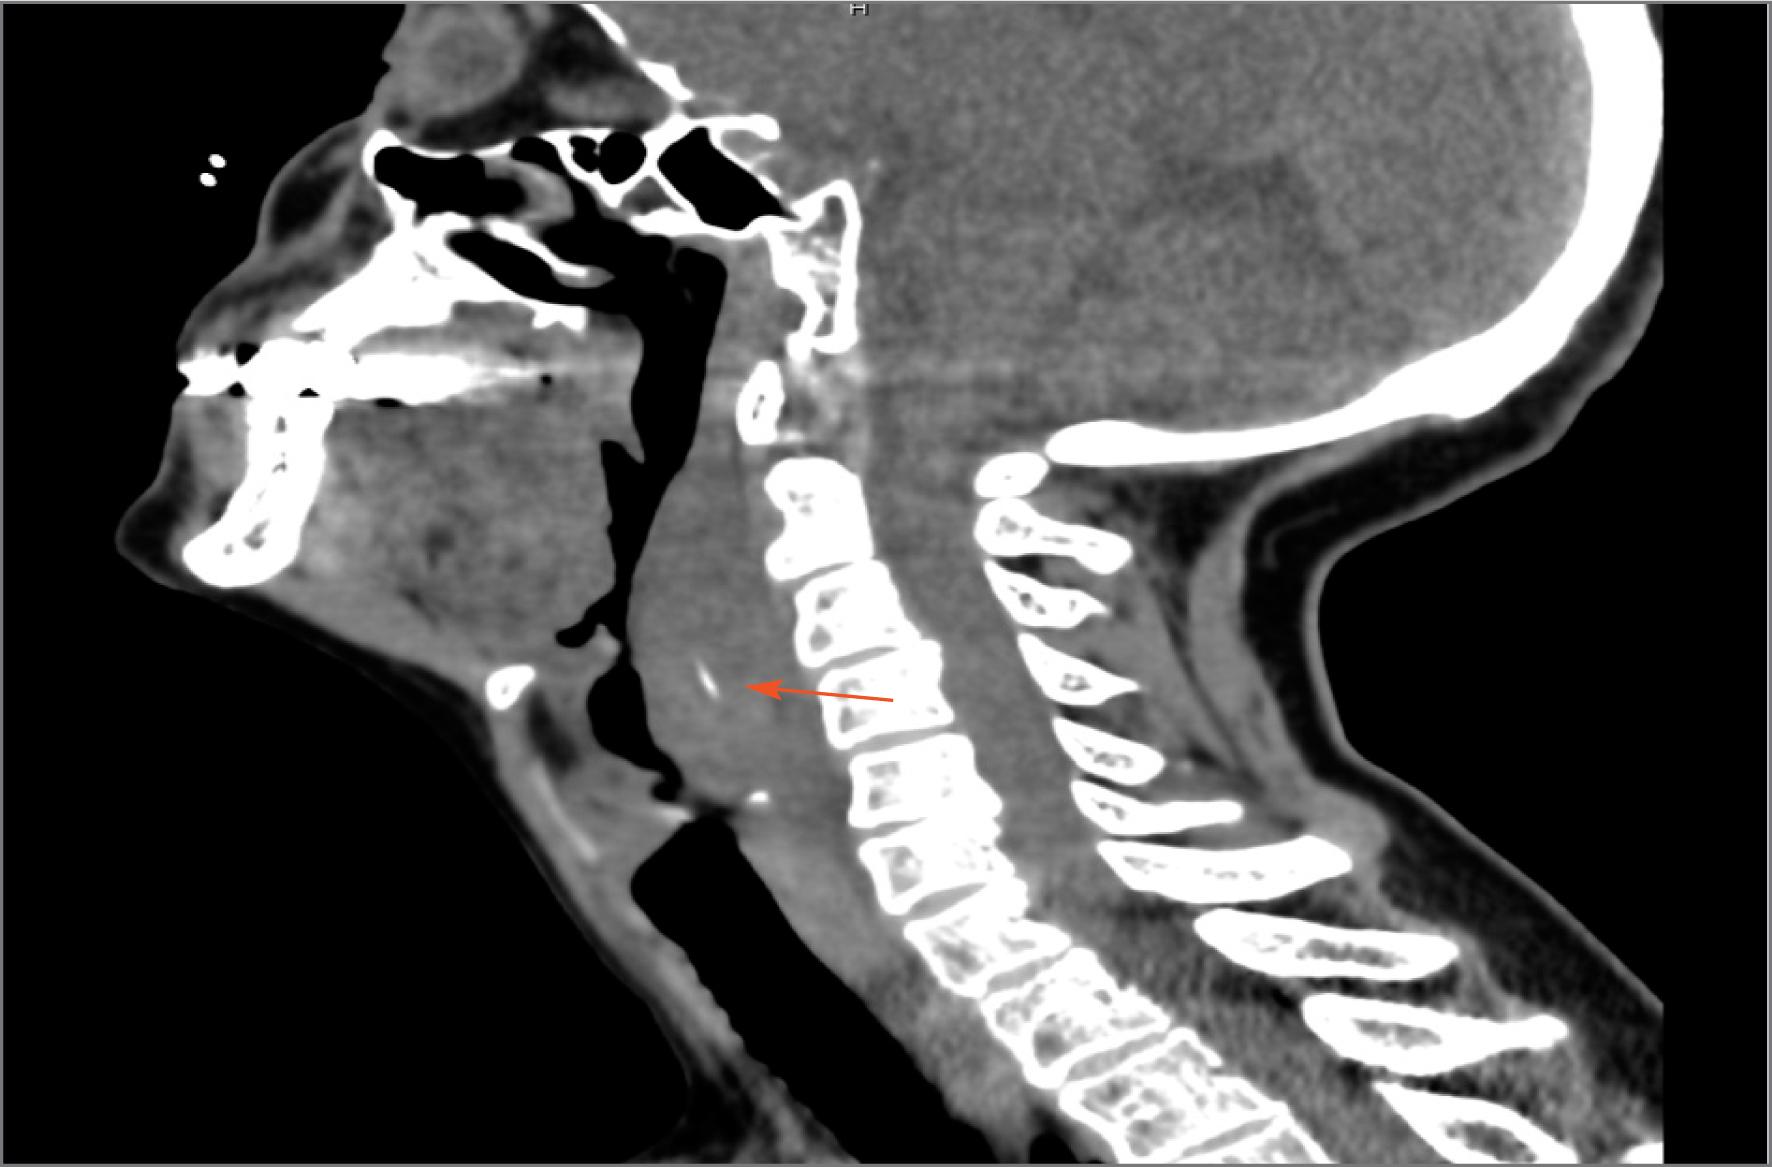

Fig. 1

CT scan of sagittal section: prevertebral soft tissue swelling with a fish bone – arrow